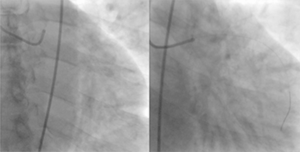

Right: The same patient after reperfusion.